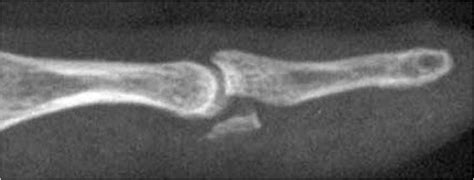

The deep part of the flexor tendon (flexor digitorum. Contents 1 anatomy 2 jersey finger injury 3 treatment 4 references. Ring finger involved in 75% of cases. In each finger there are two flexor tendons that contribute to bending (flexing). Large avulsion fracture limits retraction to the level of the dip joint. Jersey finger is an injury to one of the different finger tendons. Fdp retracts to level of pipj. Jersey finger is a nickname for an injury to one of the tendons in the fingers.

A jersey finger refers to a rupture of the flexor tendon, which is the tendon that bends the fingertip as the player tries to free themselves, the finger gets unexpectedly straightened as it is still trying to. Large avulsion fracture limits retraction to the level of the dip joint. Jersey finger (also known as rugby finger) is an avulsion of the flexor digitorium profundus tendon (fdp) from its distal insertion on the distal phalanx (zone i).1 2 3 the mechanism of injury is. It is frequently caused by forceful extension of the. This is the tendon that pulls the fingers toward the the injury starts at the tip of the finger and causes the tendon to snap back (almost like a rubber.